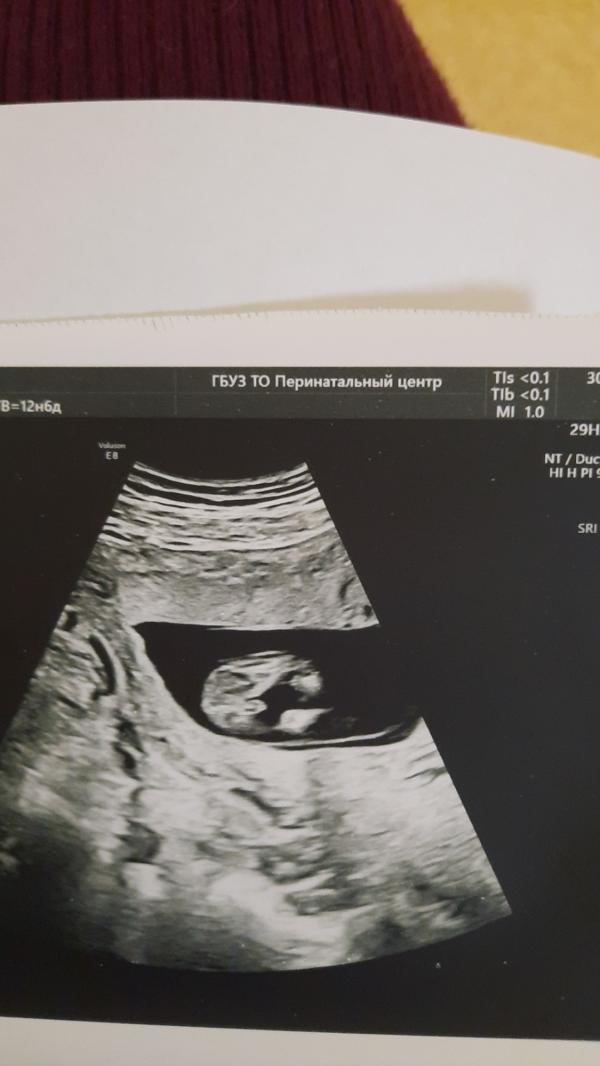

Девочки покидайте фото своих узи 13 недель пожалуйста и пол какой у вас😊 вот наши фото, на узии сначала предположили девочку, потом говорит мальчик) добавила что рано что то говорить на 100%

Ну судя по первой фотке мужичок. У моего такое же УЗИ было. Не могу на телефоне найти эту фотографию.